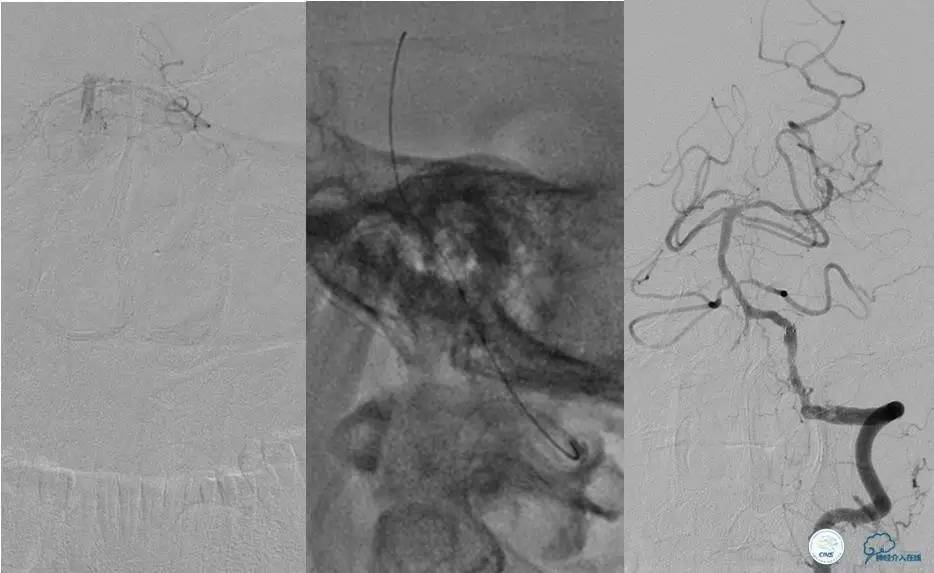

▼首先行颈动脉CTO开通术,手术顺利,Wallstent支架。

▼1周后行右侧椎动脉V4段CTO开通术。

▼微导丝穿过狭窄段,微导管造影,小球囊预扩张,2mm。

▼根据血管情况选择较大球囊再次预扩张。

▼置入2枚Wingspan支架,手术成功。

▼术后即刻CT,梗死灶内再灌注出血。

患者无症状,中性治疗。4月21日电话随访,一般情况好,当地CT示出血吸收期。